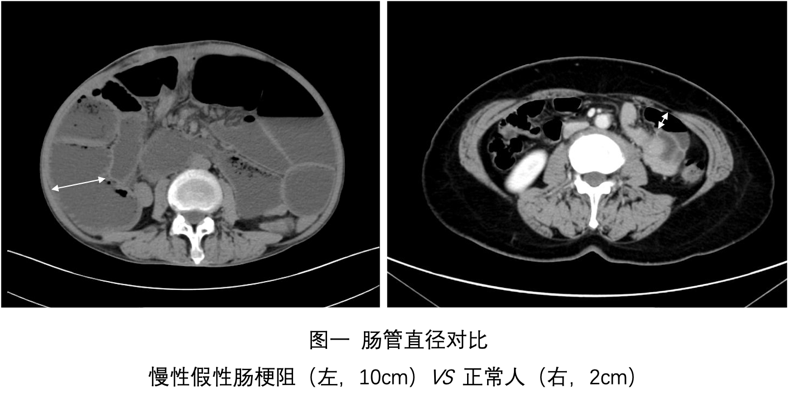

肠梗阻是指肠内容物无法正常通过肠道,导致患者腹胀、腹痛、呕吐、排便、排气停止。该病病因众多,假性肠梗阻是其中一种罕见类型。该病具有典型肠梗阻临床表现(图一、二),病变在肠壁本身(肠壁神经、肌肉和间质),肠腔并无机械性梗阻。病程超过6个月称为慢性假性肠梗阻。

临床表现为典型肠梗阻症状,并无特异性。肠动力差导致肠道细菌过度增殖,引起营养吸收不良、脂肪泻、体重下降及维生素缺乏,甚至引发营养相关并发症。部分病例出现泌尿系统症状。此病误诊率极高,多数患者发病到确诊平均需要8年,88%患者平均接收3次的手术(图三),就诊时病情处于晚期。